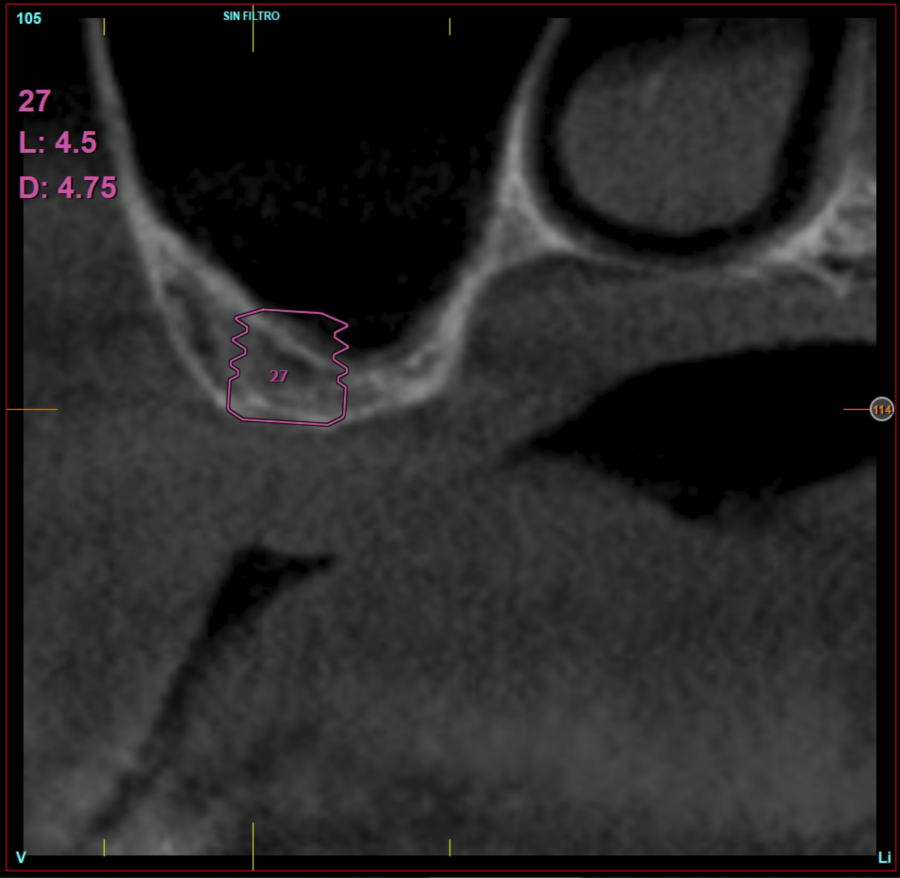

In all cases, a diagnosis was made based on study models, intraoral examination of the patient and performing a Cone-beam analysed using the specific BTI-Scan 3 software (Biotechnology Institute, Vitoria, Alava, Spain).

Ten patients who met the inclusion criteria were recruited, in which 20 implants were inserted. Three of them were women with an average age of 72 (+/- 6 years). None of the patients were smokers at the time of surgery and did not have any active periodontal disease. The majority of the implants diameter included in the study was 5 mm (60%), followed by 4.5, 5.5 and 4.75 mm (13.33% each). The predominant length was 5.5 mm (86.6% of the cases), with 13.4% of the remaining implants with a length of 4.5 mm. The most common positions were for the second molars (molars 27 and 17) representing 55% of the cases.

Figures 2-19 show one of the cases included in the study.